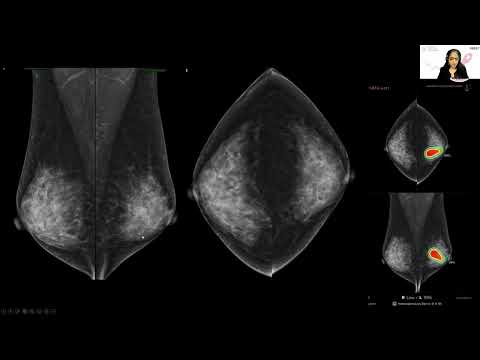

Local doctors use artificial intelligence to get a closer look at breast imaging